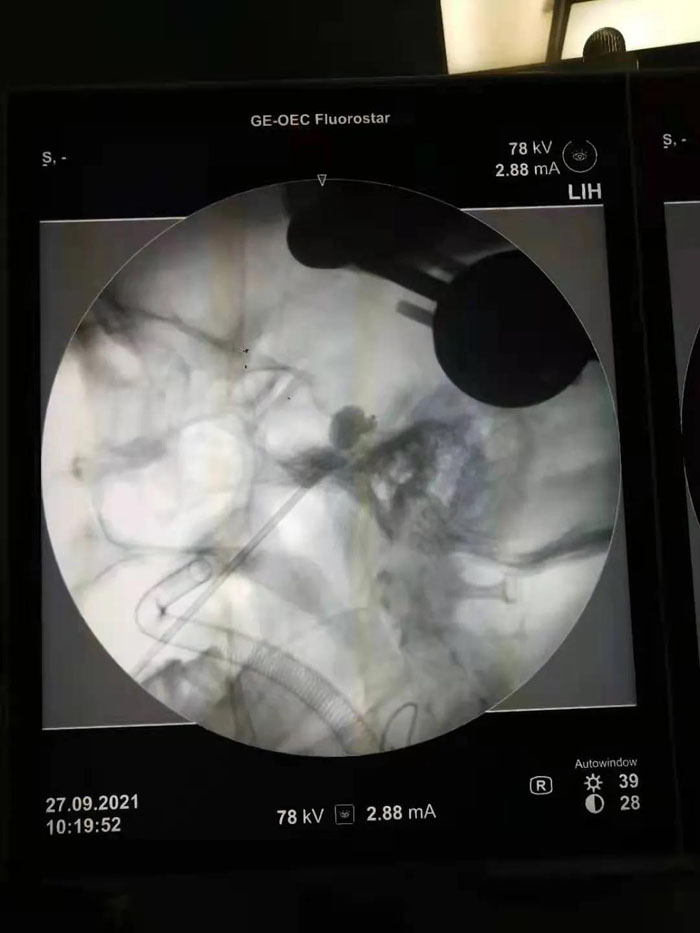

病例1.患者年近八旬,患有三叉神經(jīng)痛多年,疼痛發(fā)作起來痛不欲生,吃飯、洗臉都成了奢望。曾兩次到濟南某省級醫(yī)院行射頻、藥物注射等治療,無明顯效果。續(xù)繼軍主任團隊術前仔細研判患者病情,認為患者年齡大,開顱手術風險較高。三叉神經(jīng)半月節(jié)球囊壓迫術具有微創(chuàng)、恢復快、費用低的優(yōu)勢,更適合老年患者及復發(fā)患者。但該手術需要精確定位,手術最大的挑戰(zhàn)是要把穿刺針準確穿入近10cm外的卵圓孔,而該孔僅有3mm的大小,難度不亞于射擊比賽中“百步穿楊”。傳統(tǒng)方法只能在C形臂引導下徒手進行,穿刺成功率低。在續(xù)繼軍主任指導下,丁鵬、吳開福主治醫(yī)師采用機器人輔助穿刺,術前驗證誤差僅為0.37mm,保證了一針穿刺到位,實際術中僅用10秒鐘即完成了穿刺操作,避免了重要血管、腦組織的損傷,大大降低了手術風險。術后,患者面部疼痛即基本消失,2天后順利出院。